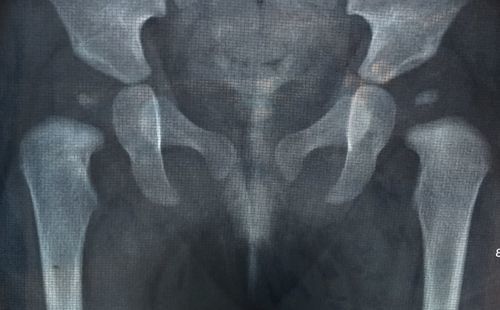

Здравствуйте. Беспокоит боль в тазобедренном суставе слева после ходьбы. Обычно проявляется после нагрузки, даже не большой. Так же постоянные боли, скованность в спине, пояснице, по утрам, после длительного нахождения на ногах. Бывает кружится голова после смены положения тела. Присутствует часто разбитость, слабость, потеря энергии. РентгенПоказать полностью... снимки приложил. Какое возможно лечение/ реабилитация в данной ситуации?

Пол: Мужской

Возраст: 36